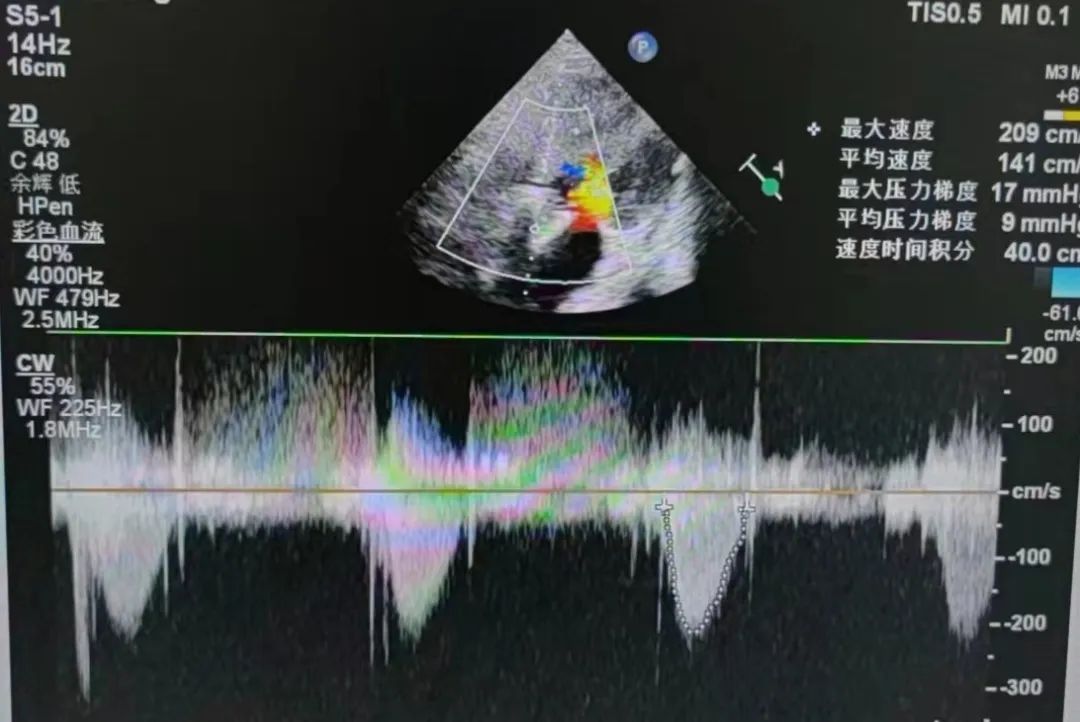

2、病史:患者于2月前反复于活动后出现气促,伴阵发性咳嗽,爬2层楼梯时即出现,休息后可缓解,无胸闷痛,无心悸,无咳粉红色泡沫痰,无恶心呕吐,遂至当地医院就诊,予对症处理后症状可改善(具体不详)。2周前,患者再次出现上述症状,性质同前,遂至我院就诊,完善心脏彩超提示AS(重度)合并AI(重度),抽血BNP:1897.30pg/ml,现患者为求进一步诊治来我院,门诊考虑"心脏瓣膜病"收入我科。

4、辅助检查:心脏彩超提示AS(重度)合并AI(重度),抽血BNP:1897.30pg/ml。

平均压差降为9mmHg平均流速降为1.41m/s

瓣膜释放后行血流动力学评估,跨瓣压差从术前100mmHg降至9mmHg,无瓣周漏,左冠脉灌注良好,手术圆满完成。